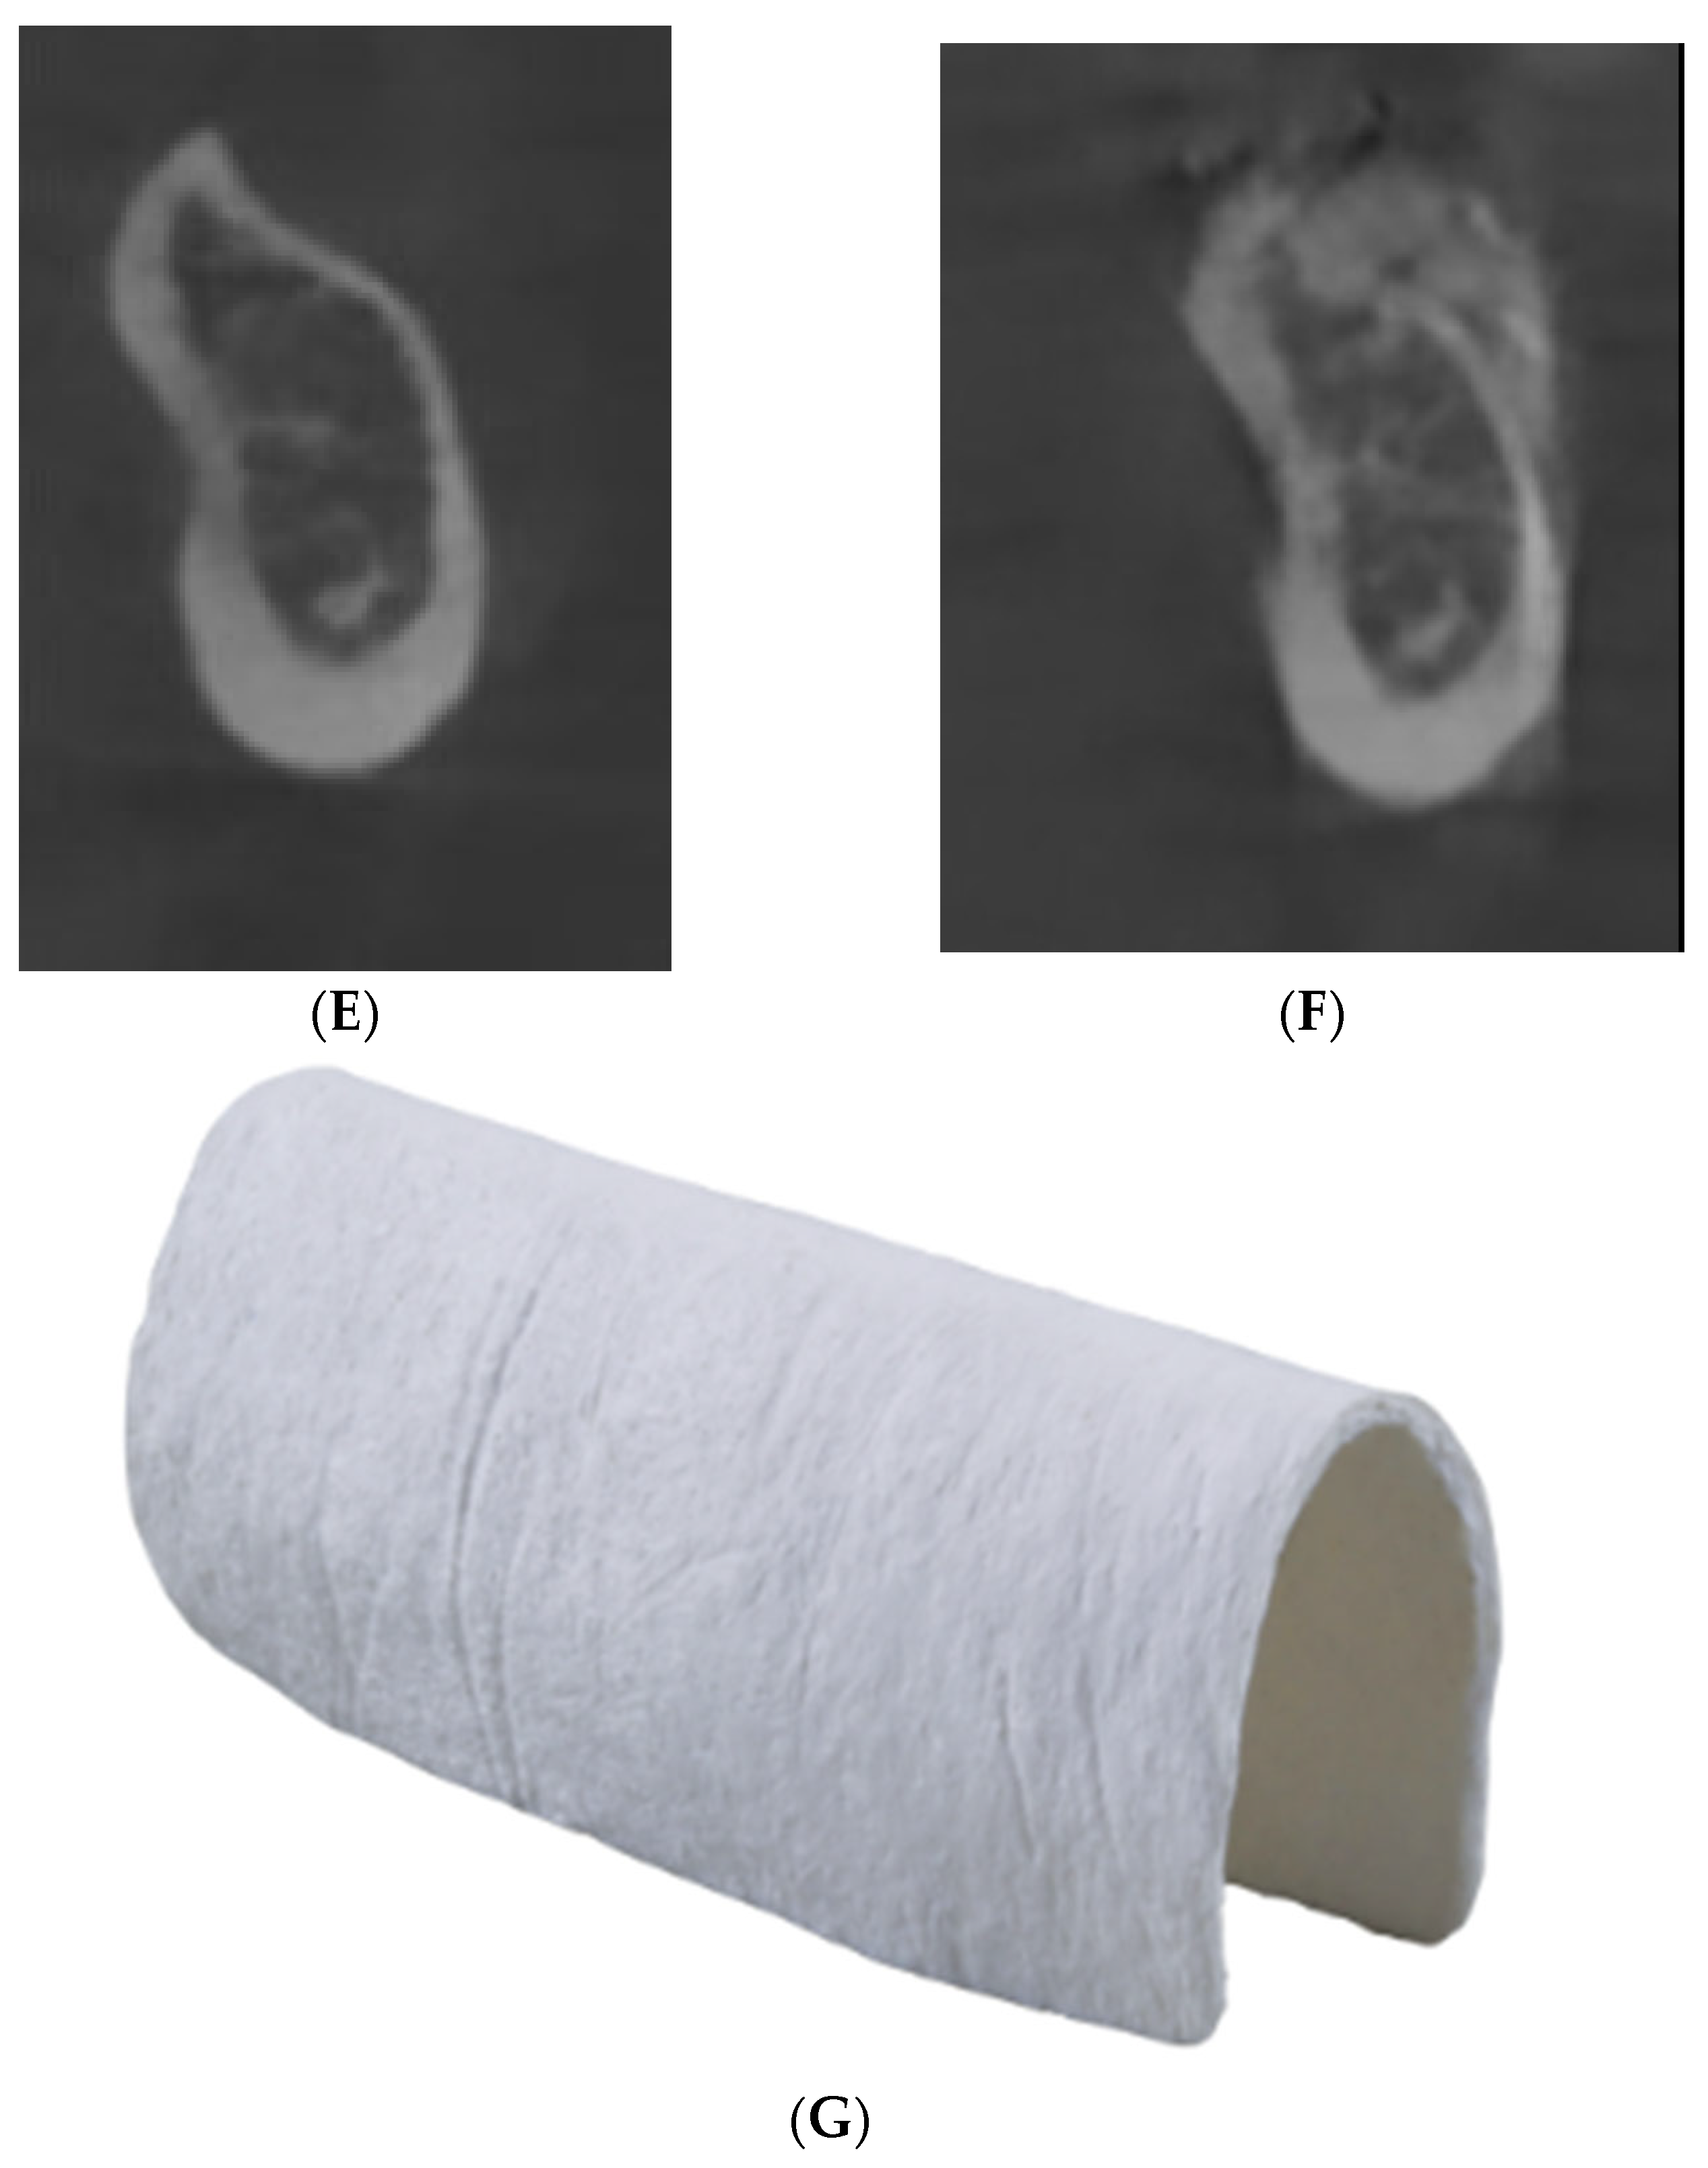

2. Materials and Methods

3. Results